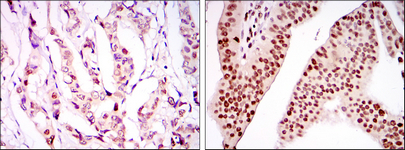

Facts about PC4 and SFRS1-interacting protein.

May play an important role in lens epithelial to fiber cell terminal differentiation. May play a protective role during stress-induced apoptosis.

Widely expressed. Expressed at high level in the thymus. Expressed in fetal and adult brain. Expressed in neurons, but not astrocytes. Markedly elevated in fetal as compared to adult brain. In the adult brain, expressed in the subventricular zone (SVZ), in hippocampus, and undetectable elsewhere. In the fetal brain, expressed in the germinal neuroepithelium and cortical plate regions.

Nucleus. Remains chromatin-associated throughout the cell cycle.